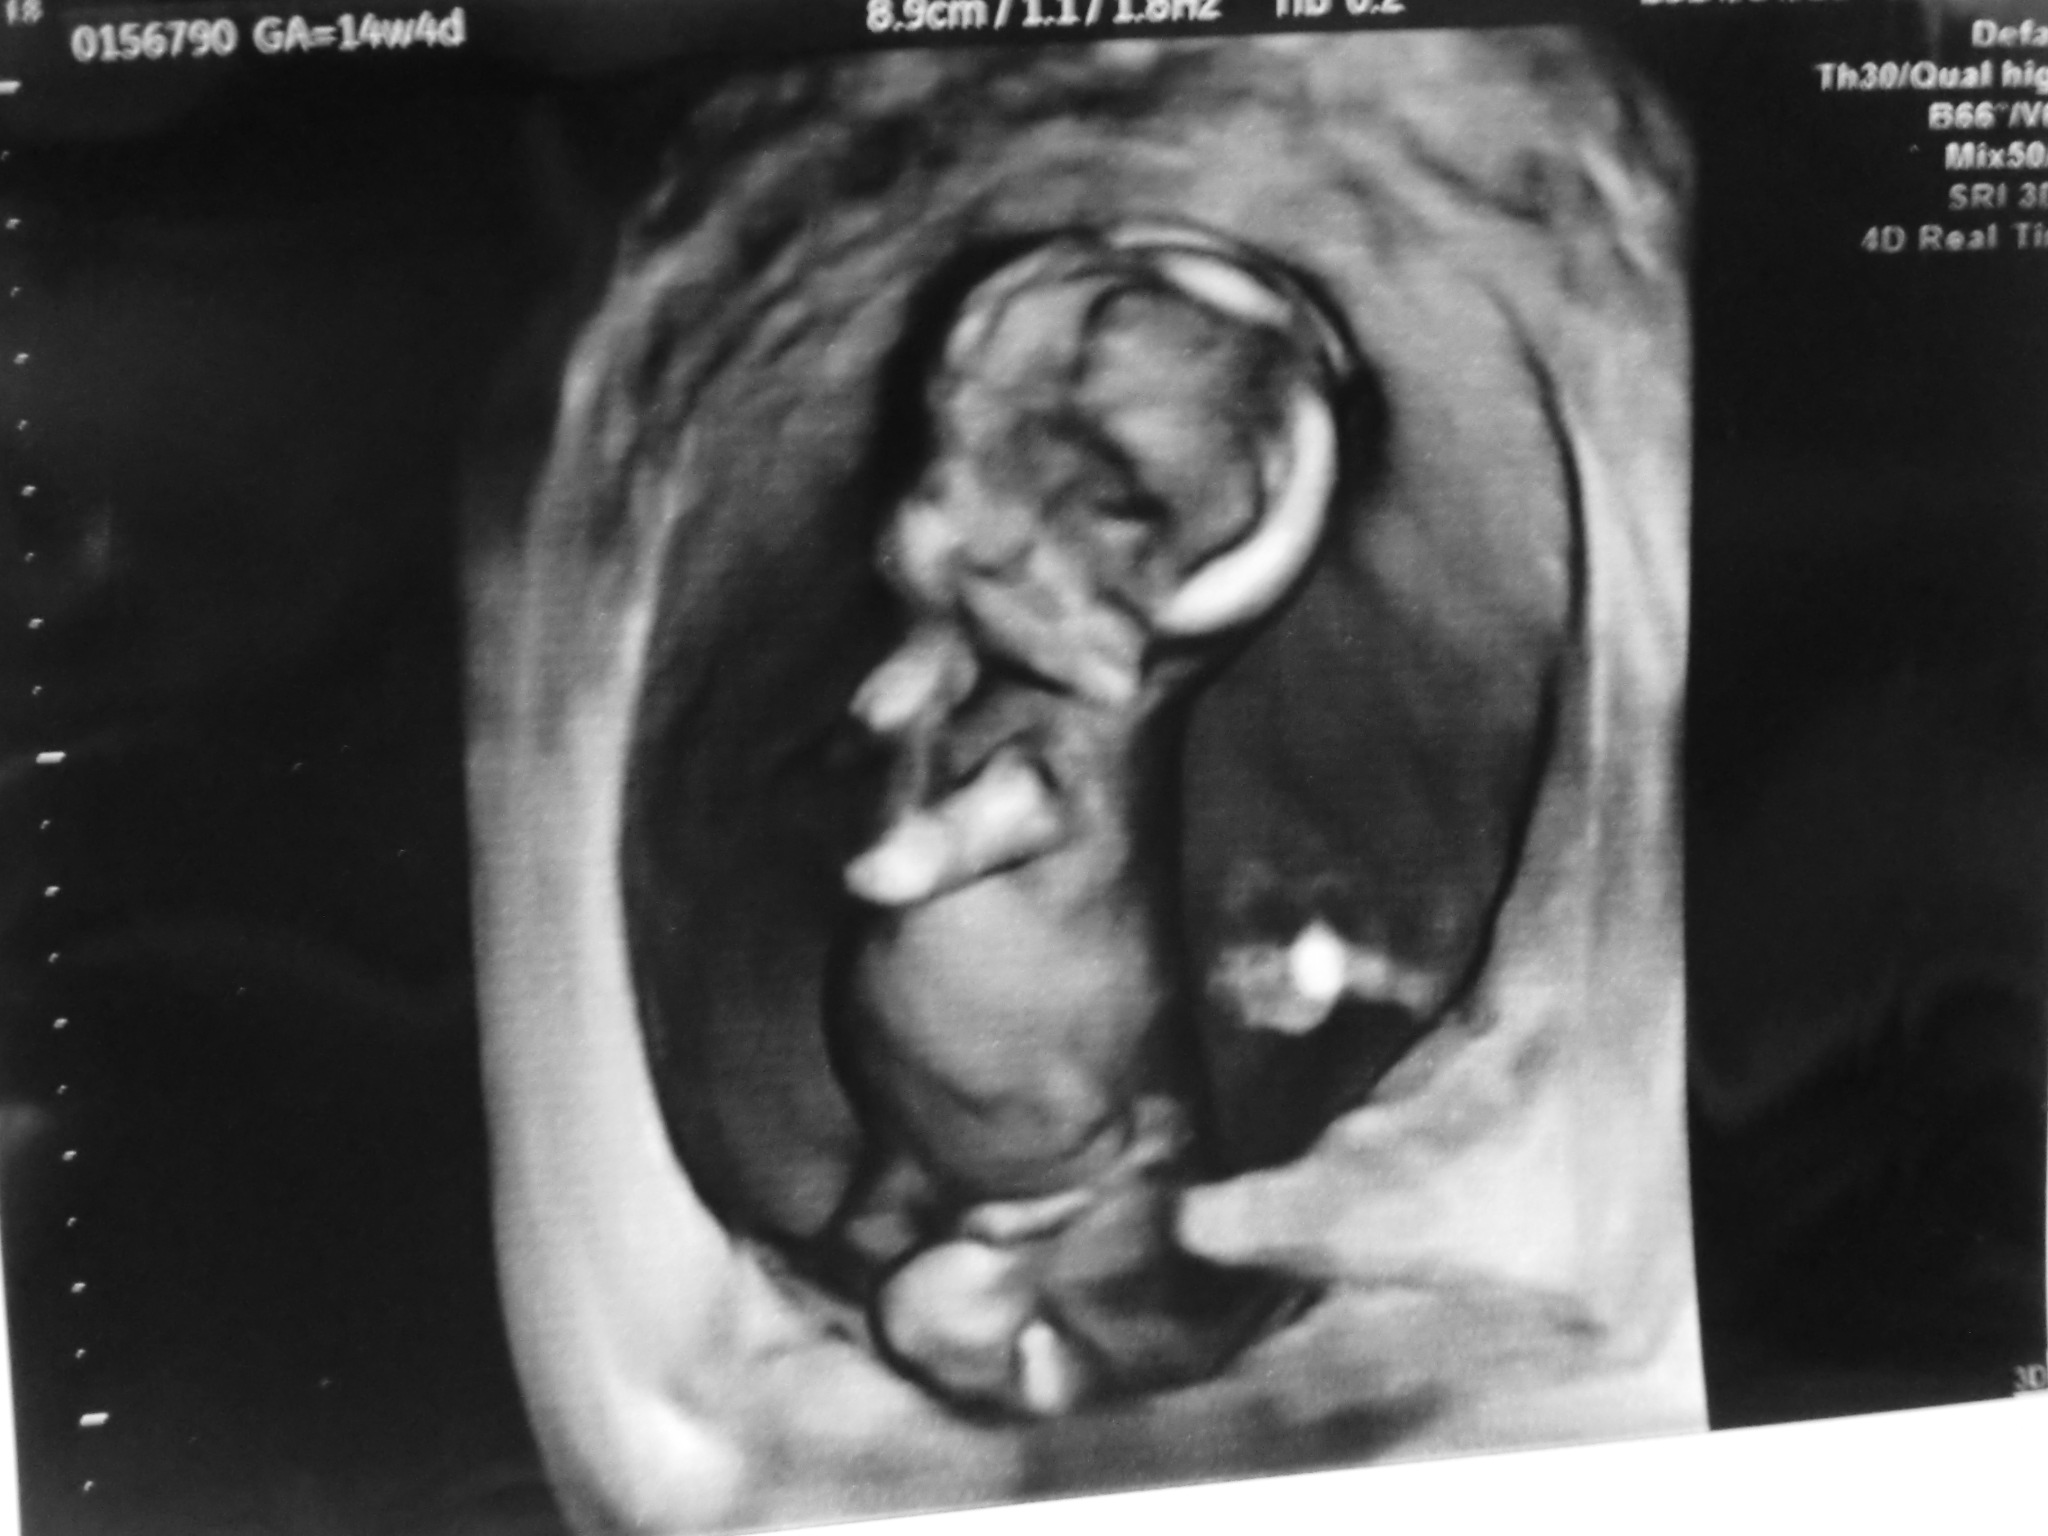

今回からは股おっぴろげずに済みました。腹からエコー(でも思ってる以上にパンツめくらないといけないからあらわ)

今回から初の4D画像です!

モニターでは肌色というかオレンジ色というか、そういう色で動いてるのを見えてますが(動いてるのは前のでも見えてるけど)

印刷すると白黒です。(病院によるのかな?)

かわいいw

正座して、手を口元に当ててるんだぜ?

なんかお上品じゃないか!

先生がこの縦画像で見せてくれたけど、正しくは腹に対してうつぶせの体勢らしいですちょうど左が下になる。

体長10センチほどです。